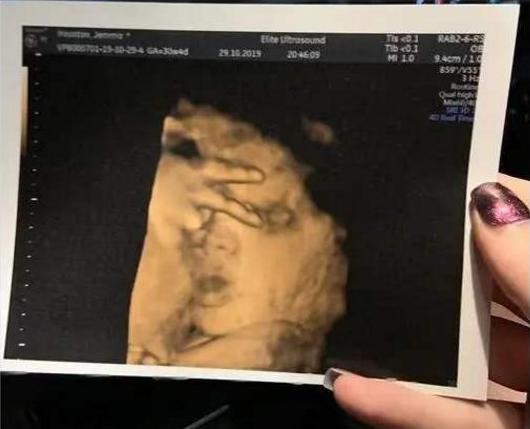

要说孩子的镜头感还真的是娘胎里带的,别说你不信,这个宝妈就分享了自己最珍贵的一张B超照片,因为这张照片可以说是要不是亲眼所见,谁都不敢相信这是一个小胎儿自发有的镜头感,这也是宝妈去做产检,然后再拍B超的时候宝宝就超级配合。

在医生确认完胎儿的身体发育没有什么问题的时候,准备给宝妈拍一张B超照片拿回去,结果就在这个时候宝宝突然就举起小手正好放在眼睛周围,还比了一个耶,这让当时所有在场的人都愣住了,不得不说妈妈爱拍照这一点还真是从小就会遗传给宝宝。